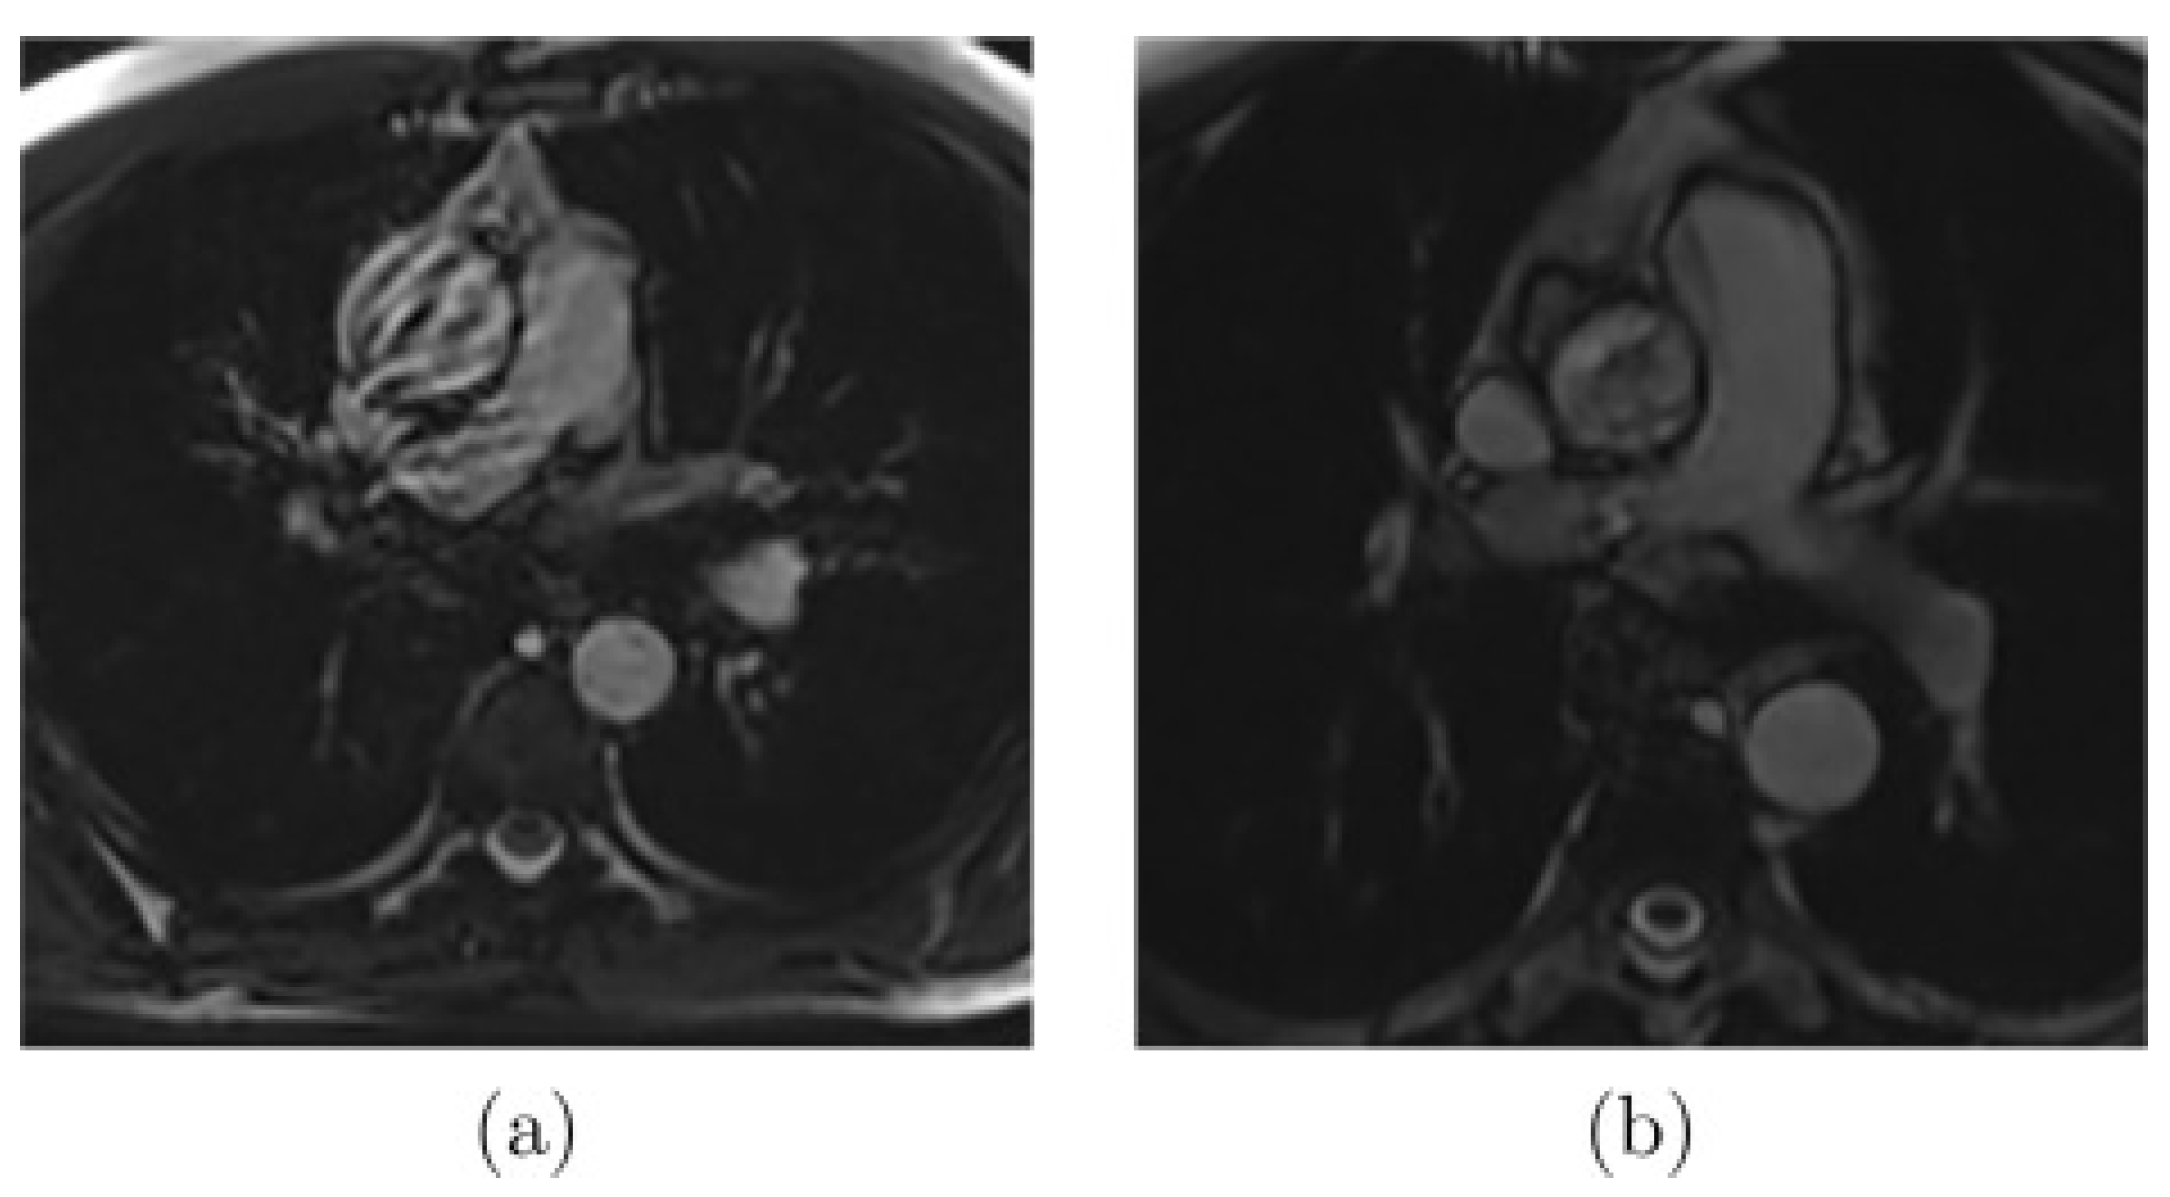

As presented in Figure 2, there are images where noise or artifacts are often present in the critical part of the cardiac cycle, especially for the ascending aorta, as the FLASH sequence is sensitive to rapid and turbulent flow. Another extreme case that complicates the segmentation (Figure 3a) appears when the aortic border is poorly visible due to the proximity of some other structures. Finally, other common difficulties can be encountered, such as the highly dilated ascending aorta as shown in Figure 3b.

Figure 2.

Examples of MR images with artifacts due to (a) rapid or (b) turbulent blood flow [20].